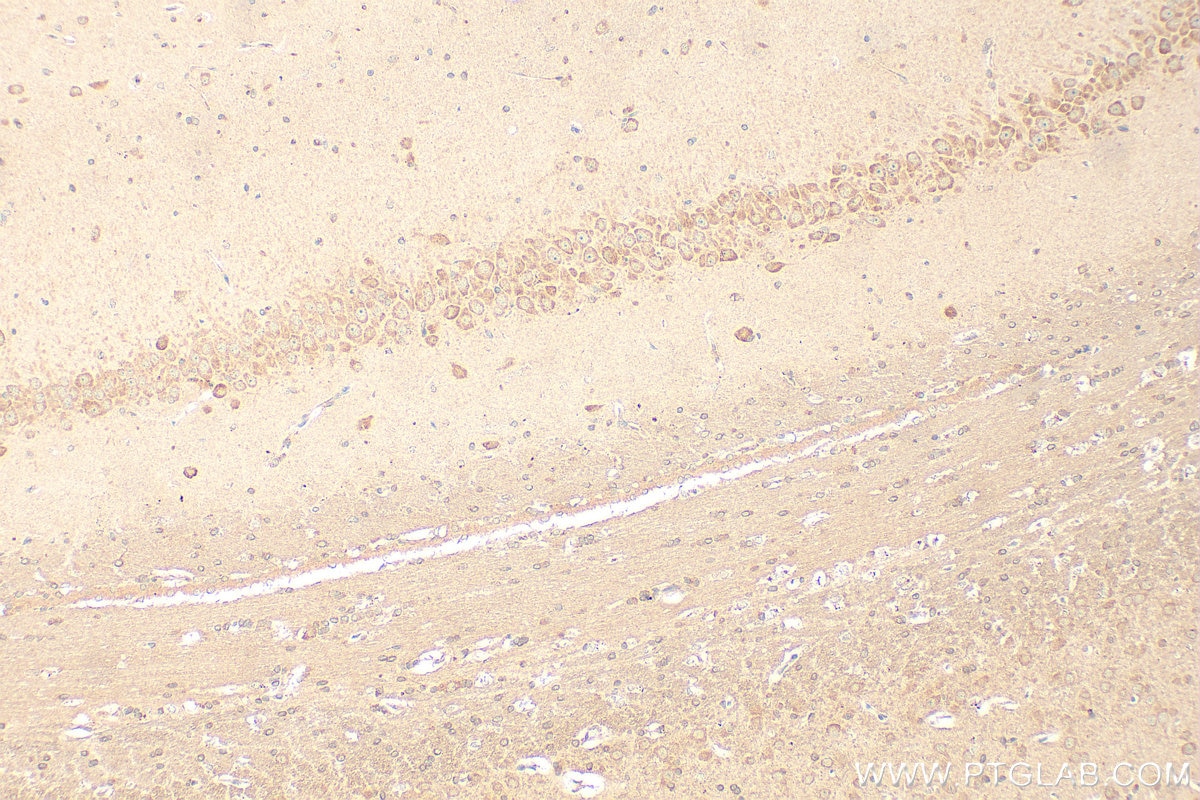

67089-1-PBS targets CNTN2 in WB, IHC, IF-P, Indirect ELISA applications and shows reactivity with human, mouse, pig samples.